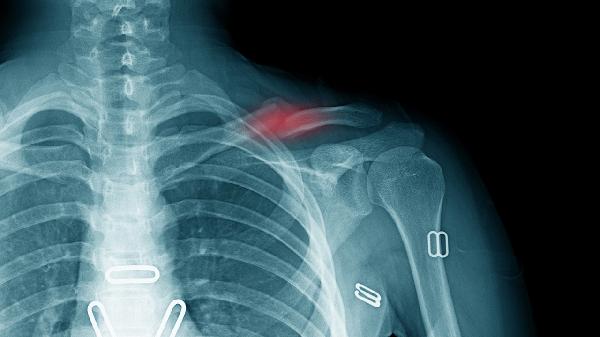

2、外伤后遗症

锁骨骨折愈合后或软组织挫伤可能遗留间歇性疼痛。触摸时可能有压痛感,阴雨天症状明显。急性期可用双氯芬酸钠凝胶外涂,慢性期建议进行超声波治疗帮助组织修复。